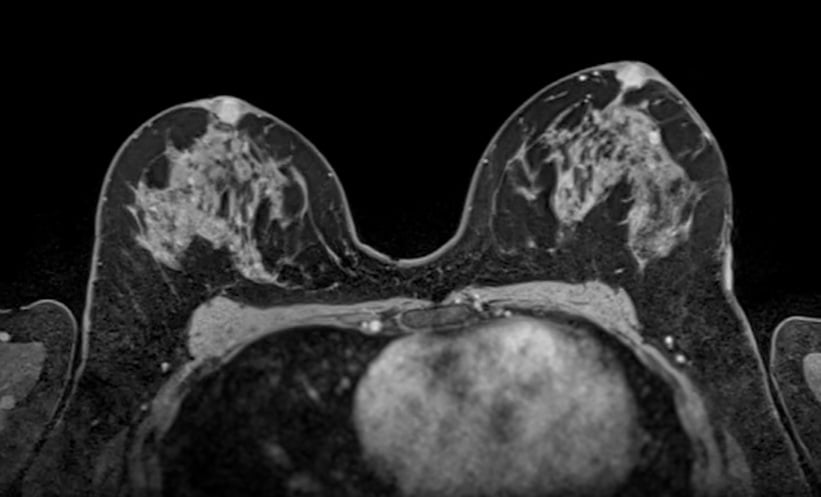

Gadopiclenol is a next-generation macrocyclic gadolinium-based contrast agent with higher T1-relaxivity, which allows strong tissue contrast at half the usual gadolinium dose. The study assessed 145 women, most with hereditary breast and ovarian cancer risk, who underwent breast MRI with 0.05 mmol/kg gadopiclenol and had a prior standard dose gadobutrol scan for comparison. Signal enhancement was measured in the breast parenchyma, aorta, and axillary lymph nodes, while two experienced radiologists rated image quality and diagnostic confidence using a standard 5-point Likert scale.

Gadopiclenol produced higher absolute enhancement in all regions studied. Breast parenchyma contrast increased by approximately 25% at later dynamic phases compared with full dose gadobutrol, with improvements of 16% in the aorta and 12% in lymph nodes. Subjective assessments showed that image quality and diagnostic confidence were rated equally or slightly better for gadopiclenol in most cases. These results suggest that high-relaxivity contrast agents can maintain or enhance diagnostic performance while reducing gadolinium exposure.